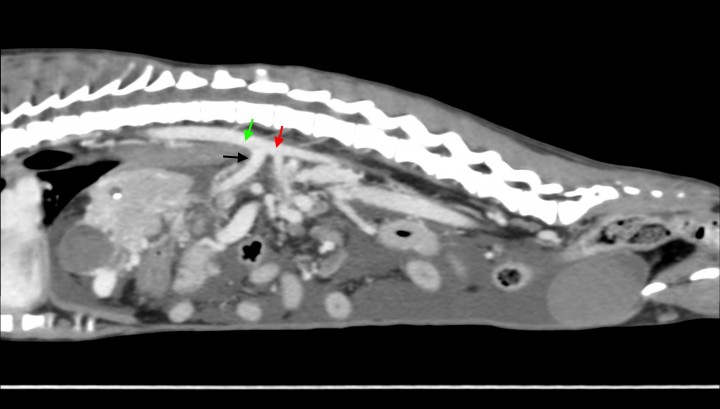

<p>Imagen de tomografía computarizada sagital tras la administración de contraste intravenoso, ventana de tejido blando. Se observa el tronco celíaco dilatado (flecha negra) con disminución del tamaño de la aorta abdominal caudal al mismo (flecha roja). Aorta abdominal craneal al tronco celíaco (flecha verde).</p>

Figura 6

Imagen de tomografía computarizada sagital tras la administración de contraste intravenoso, ventana de tejido blando. Se observa el tronco celíaco dilatado (flecha negra) con disminución del tamaño de la aorta abdominal caudal al mismo (flecha roja). Aorta abdominal craneal al tronco celíaco (flecha verde).

La TC reveló una microhepatía asimétrica, con los lóbulos hepáticos izquierdos de menor tamaño que los derechos y focos de mineralización distrófica, un gran volumen de efusión abdominal (Fig. 5) y edema de páncreas. El tronco celíaco se encontraba anormalmente dilatado y la aorta abdominal caudal a éste disminuida de tamaño (Fig. 6).